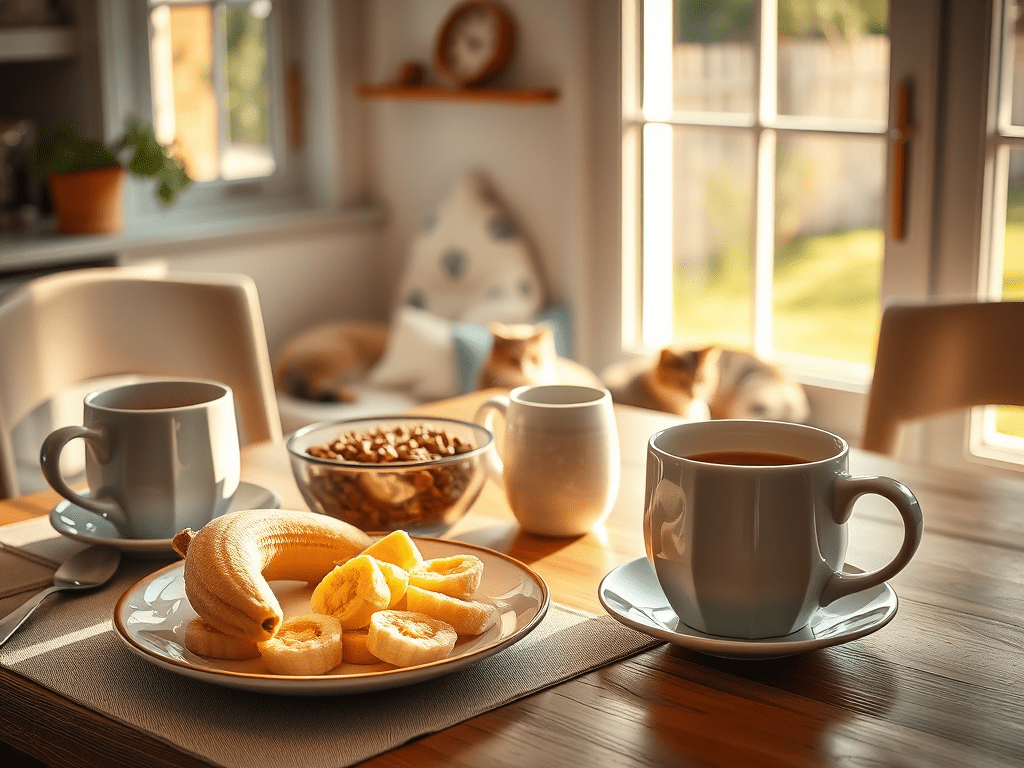

I had my breakfast first thing like usual. Watched some news and shows then got busy with some remote work. Checked in with my assistant. All good there. I had to cancel a dental cleaning for tomorrow so I called them and left a message. I told them about my diagnosis and they were very compassionate with me. Then the phone starts ringing. I had a nutritionist zoom call at 9 today. That lasted about 30-40 minutes. We discussed meals and things I eat. I asked what I’ve heard about vegan diet and she said don’t do it. Keep your protein high and dairy high but low fat. She said my meal prep for breakfast was great and I have a good system doing that and saving money.

I have bloodwork pre chemo stuff scheduled for tomorrow at 8am. It’s fasting, I’m not looking forward to that. They actually wanted me in around 2-3pm for fasting bloodwork. Are you nuts? I can’t go all day without eating, especially taking my meds that require food. Insanity for even asking for that late appointment.